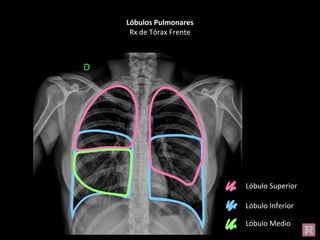

Lóbulos Pulmonares

Rx de Tórax Frente

Lóbulo Superior

Lóbulo Inferior

Lóbulo Medio